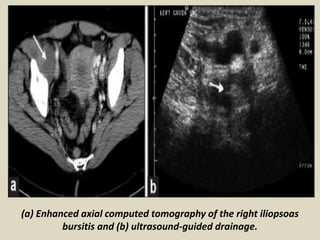

(a) Enhanced axial computed tomography of the right iliopsoas

bursitis and (b) ultrasound-guided drainage.